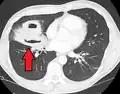

Études d'imagerie

Les abcès pulmonaires sont souvent d'un seul côté et concernent les segments postérieurs des lobes supérieurs et les segments apicaux des lobes inférieurs, car ces zones dépendent de la gravité en position couchée. La présence de niveaux air-fluide implique une rupture dans l'arbre bronchique ou, rarement, la croissance d'un organisme gazogène.[réf. nécessaire]

Abcès pulmonaire à la tomodensitométrie